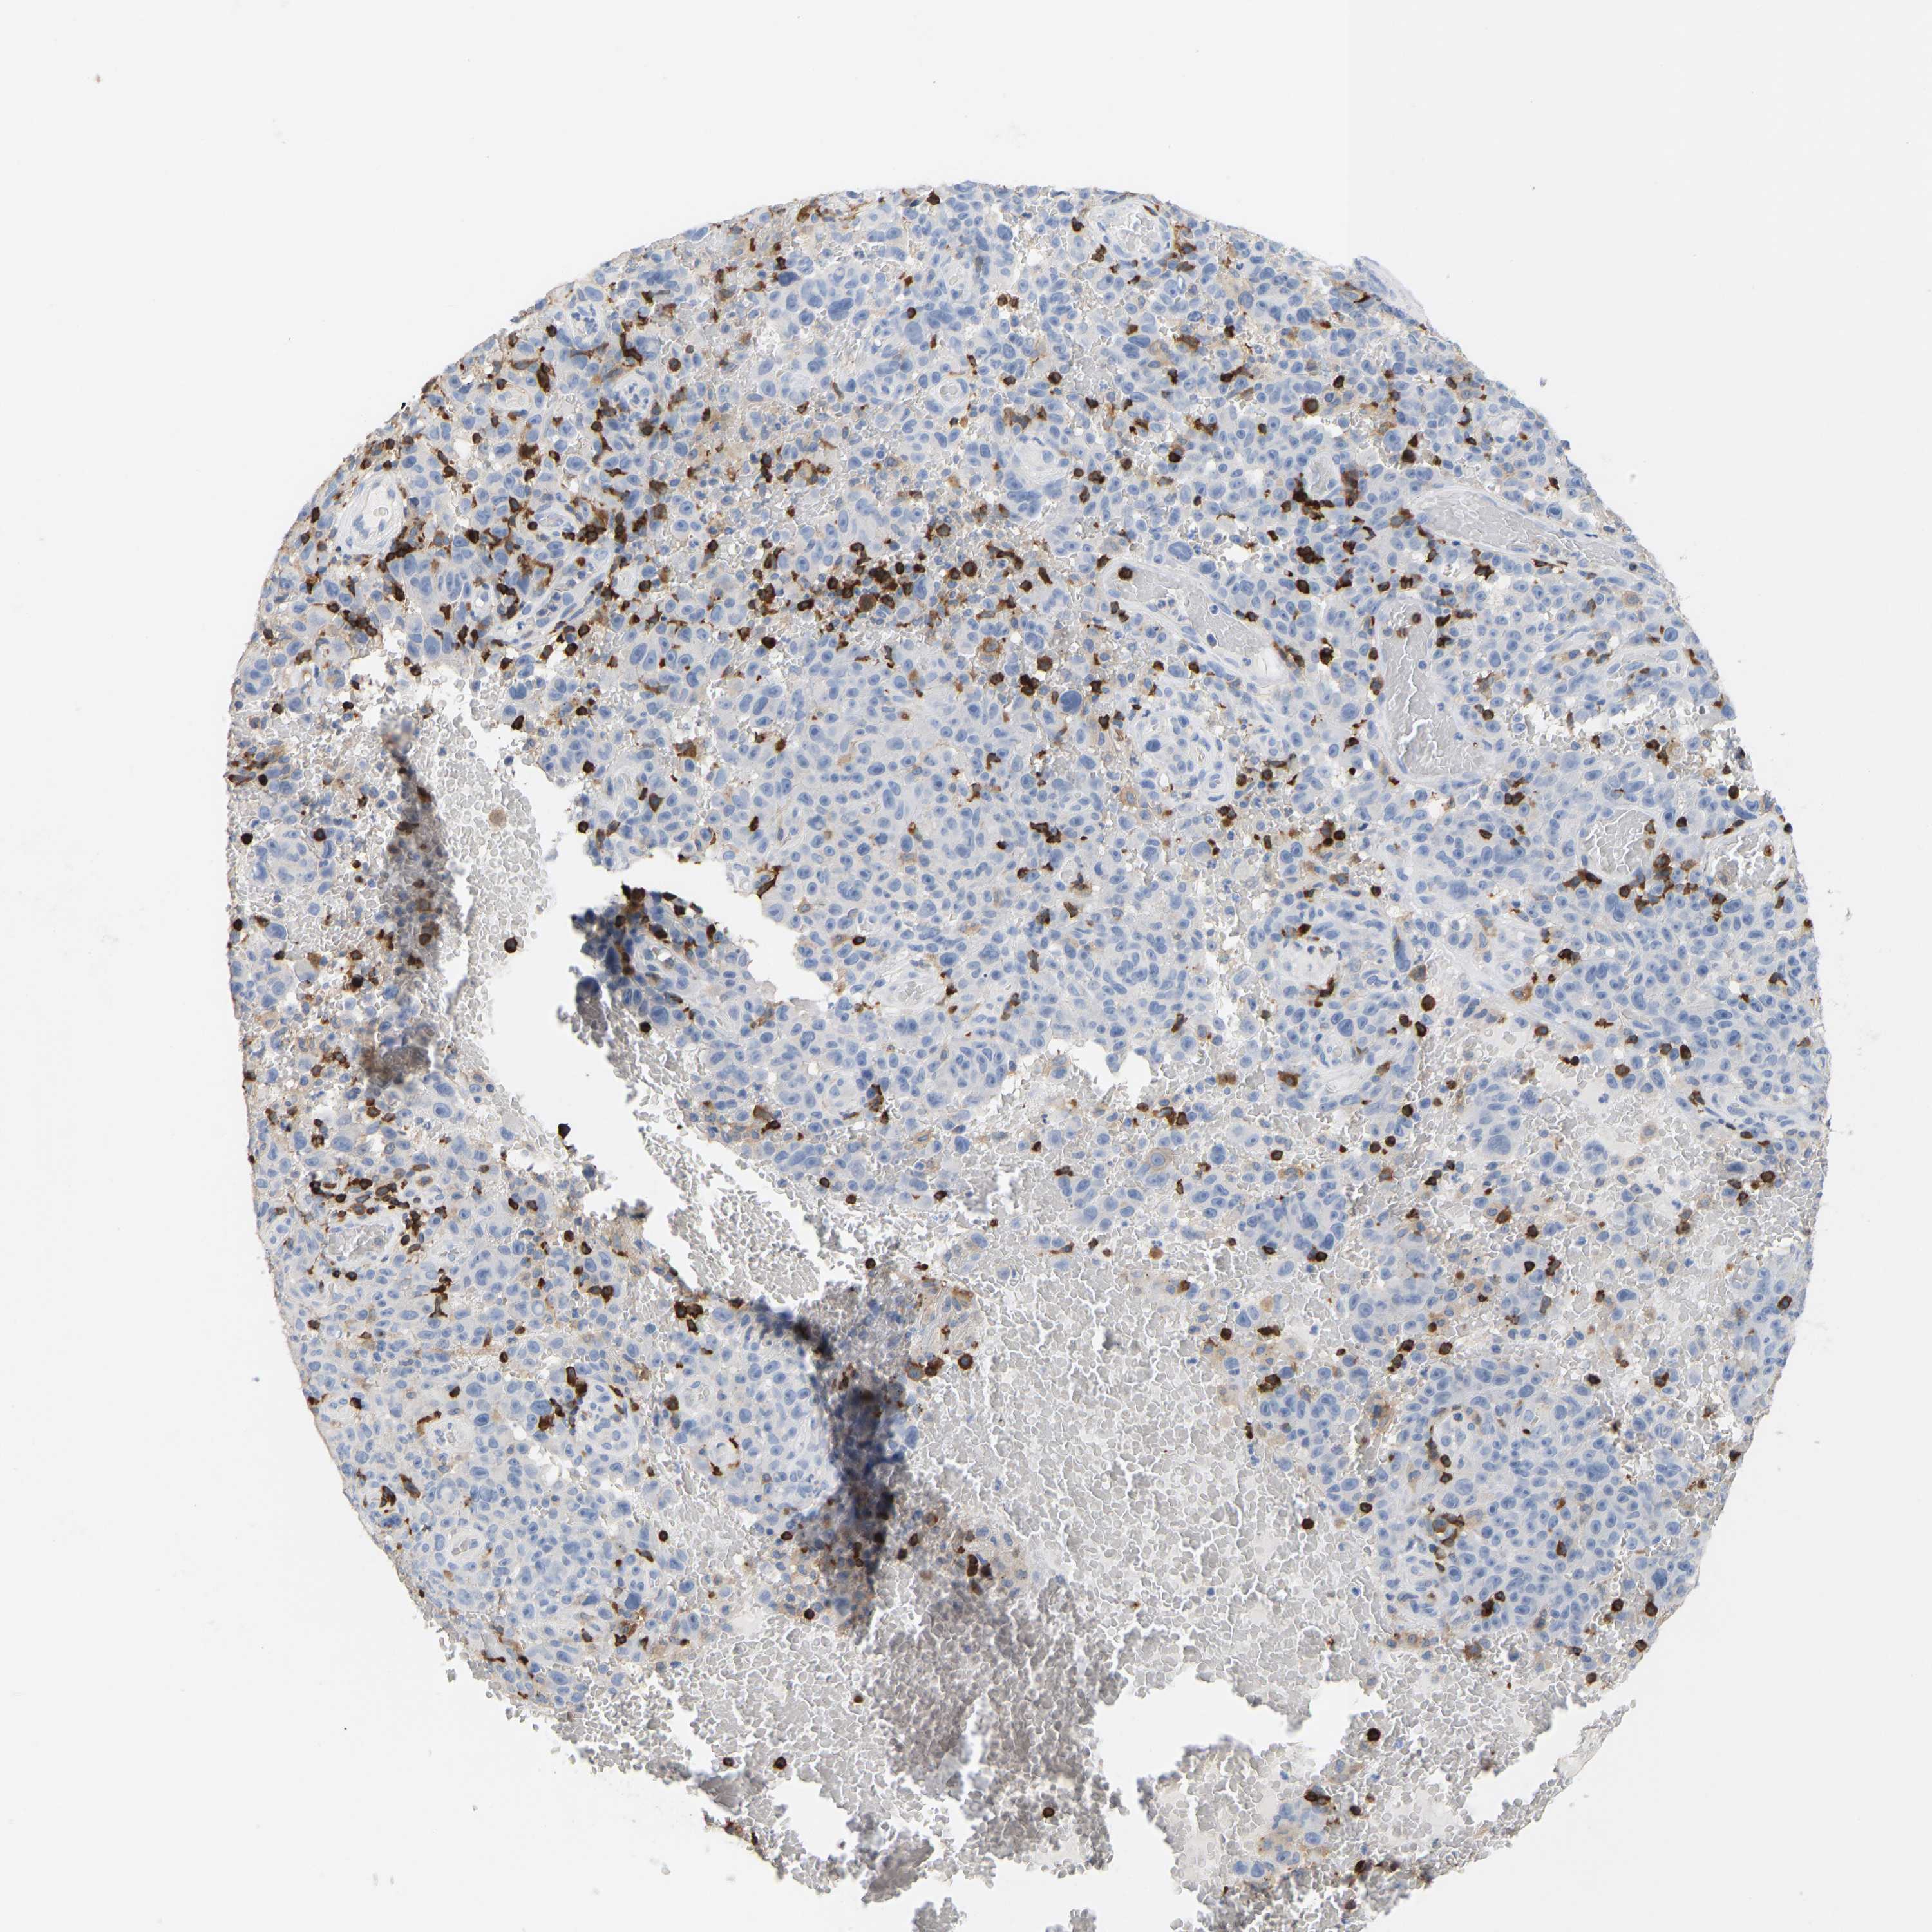

MELANOMA - Protein expressioni

A mouse-over function shows sample information and annotation data. Click on an image to view it in a full screen mode. Samples can be filtered based on level of antibody staining by selecting one or several of the following categories: high, medium, low and not detected. The assay and annotation is described here.

Note that samples used for immunohistochemistry by the Human Protein Atlas do not correspond to samples in the TCGA dataset.

Antibody stainingi

Antibody staining in the annotated cell types in the current human tissue is reported as not detected, low, medium, or high, based on conventional immunohistochemistry profiling in selected tissues. This score is based on the combination of the staining intensity and fraction of stained cells.

Each image is clickable and will lead to virtual microscopy that enables deeper exploration of all samples and also displays staining intensity scores, fraction scores and subcellular localization as well as patient and tissue information for each sample.

Antibody HPA018849

Antibody HPA019536

Antibody CAB033987

Staining

High

Medium

Low

Not detected

Intensity

Strong

Moderate

Weak

Negative

Quantity

>75%

75%-25%

<25%

None

Location

Nuclear

Cytoplasmic/membranous

Cytoplasmic/membranous,nuclear

Malignant melanoma, NOS

Malignant melanoma, Metastatic site